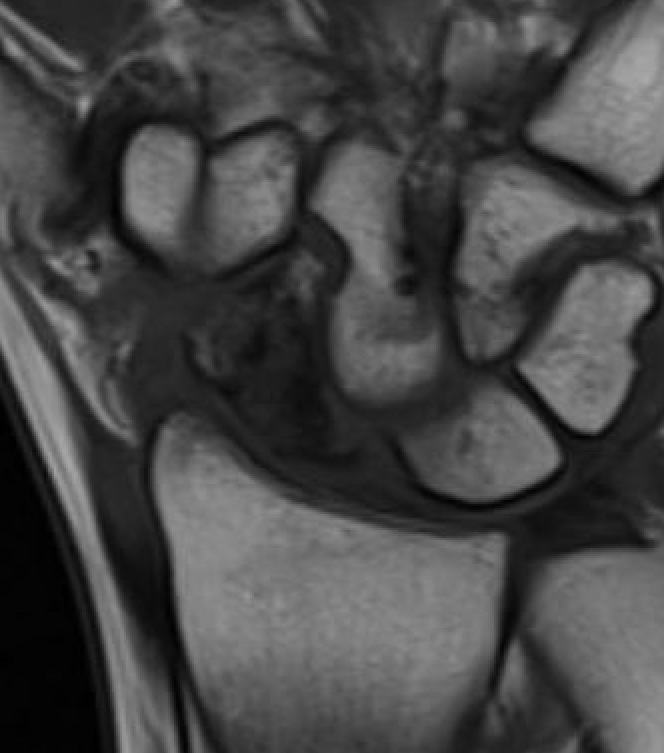

MRI

Low vascularity of scaphoid on T1 MRI and reduced gadolinium uptake proximal pole scaphoid